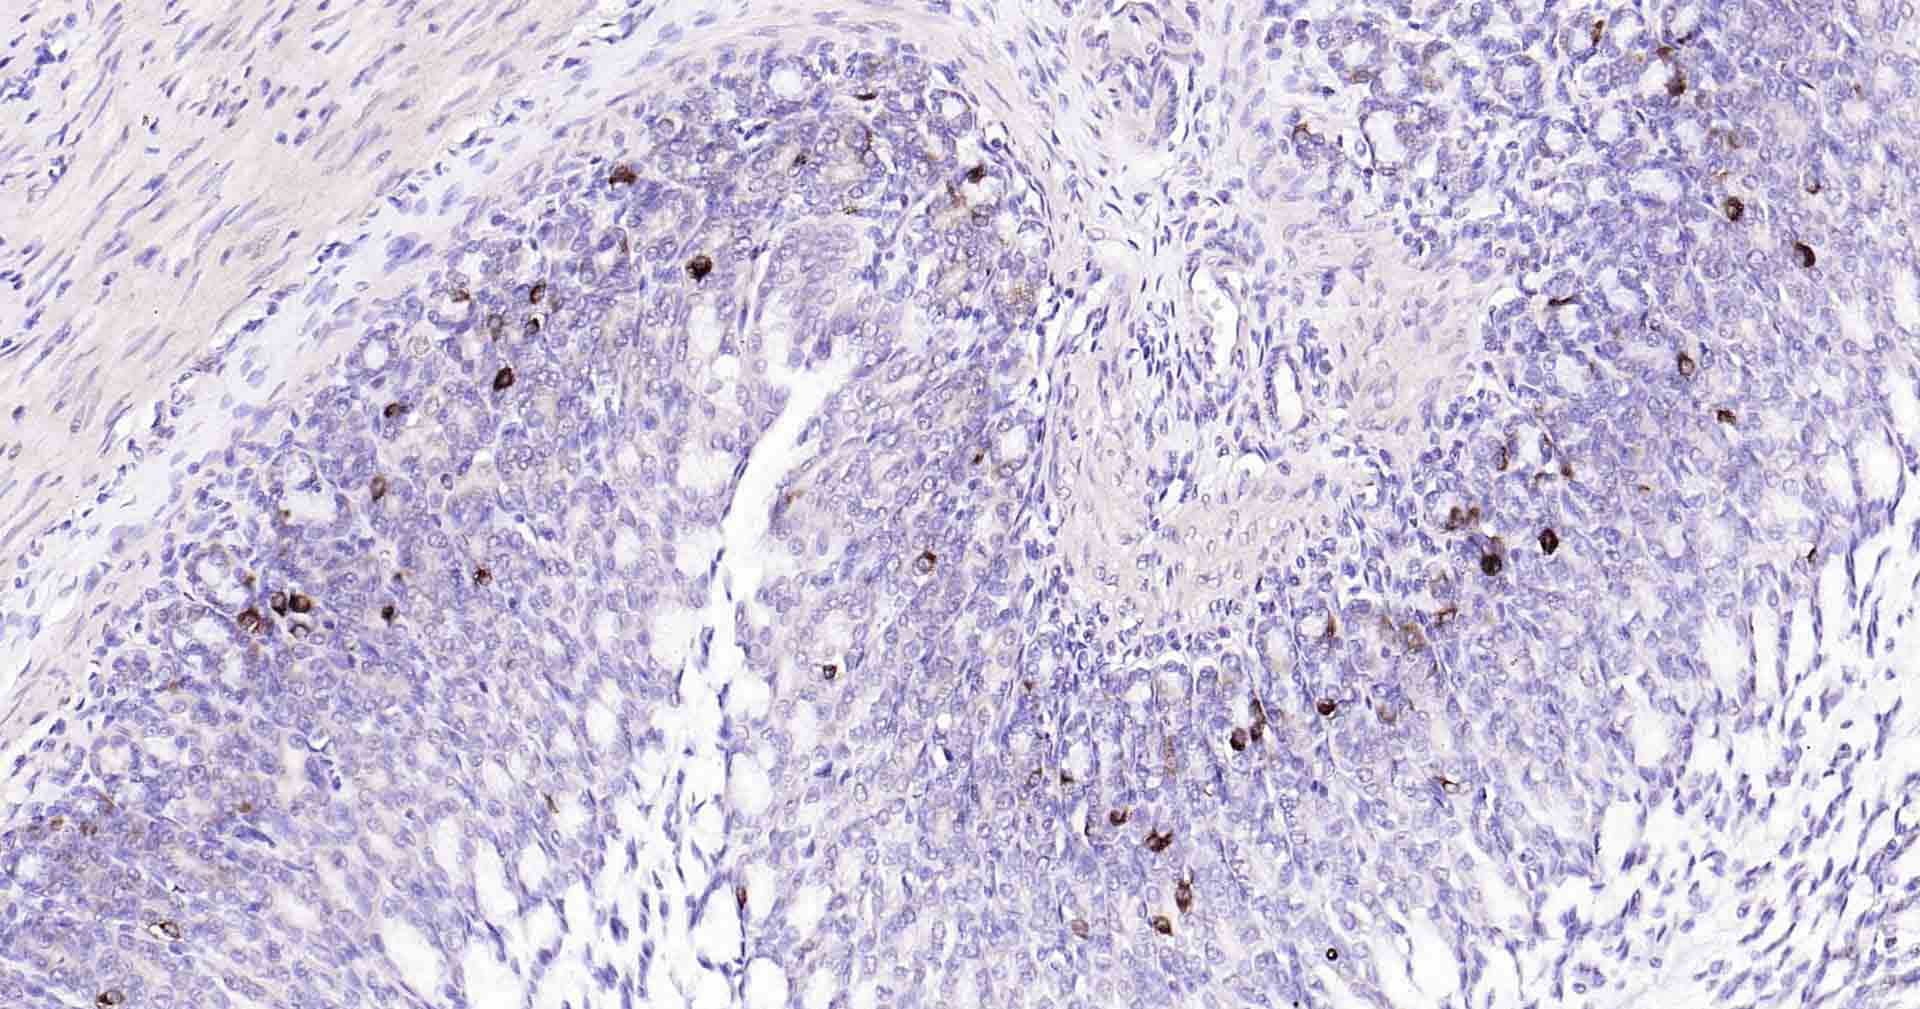

Paraformaldehyde-fixed, paraffin embedded Human Cervical Cancer; Antigen retrieval by boiling in sodium citrate buffer (pH6.0) for 15 min; Antibody incubation with Beclin 1 Monoclonal Antibody, Unconjugated(bsm-41365R) at 1:50 overnight at 4°C, followed by conjugation to the SP Kit (Rabbit, SP-0023) and DAB (C-0010) staining.